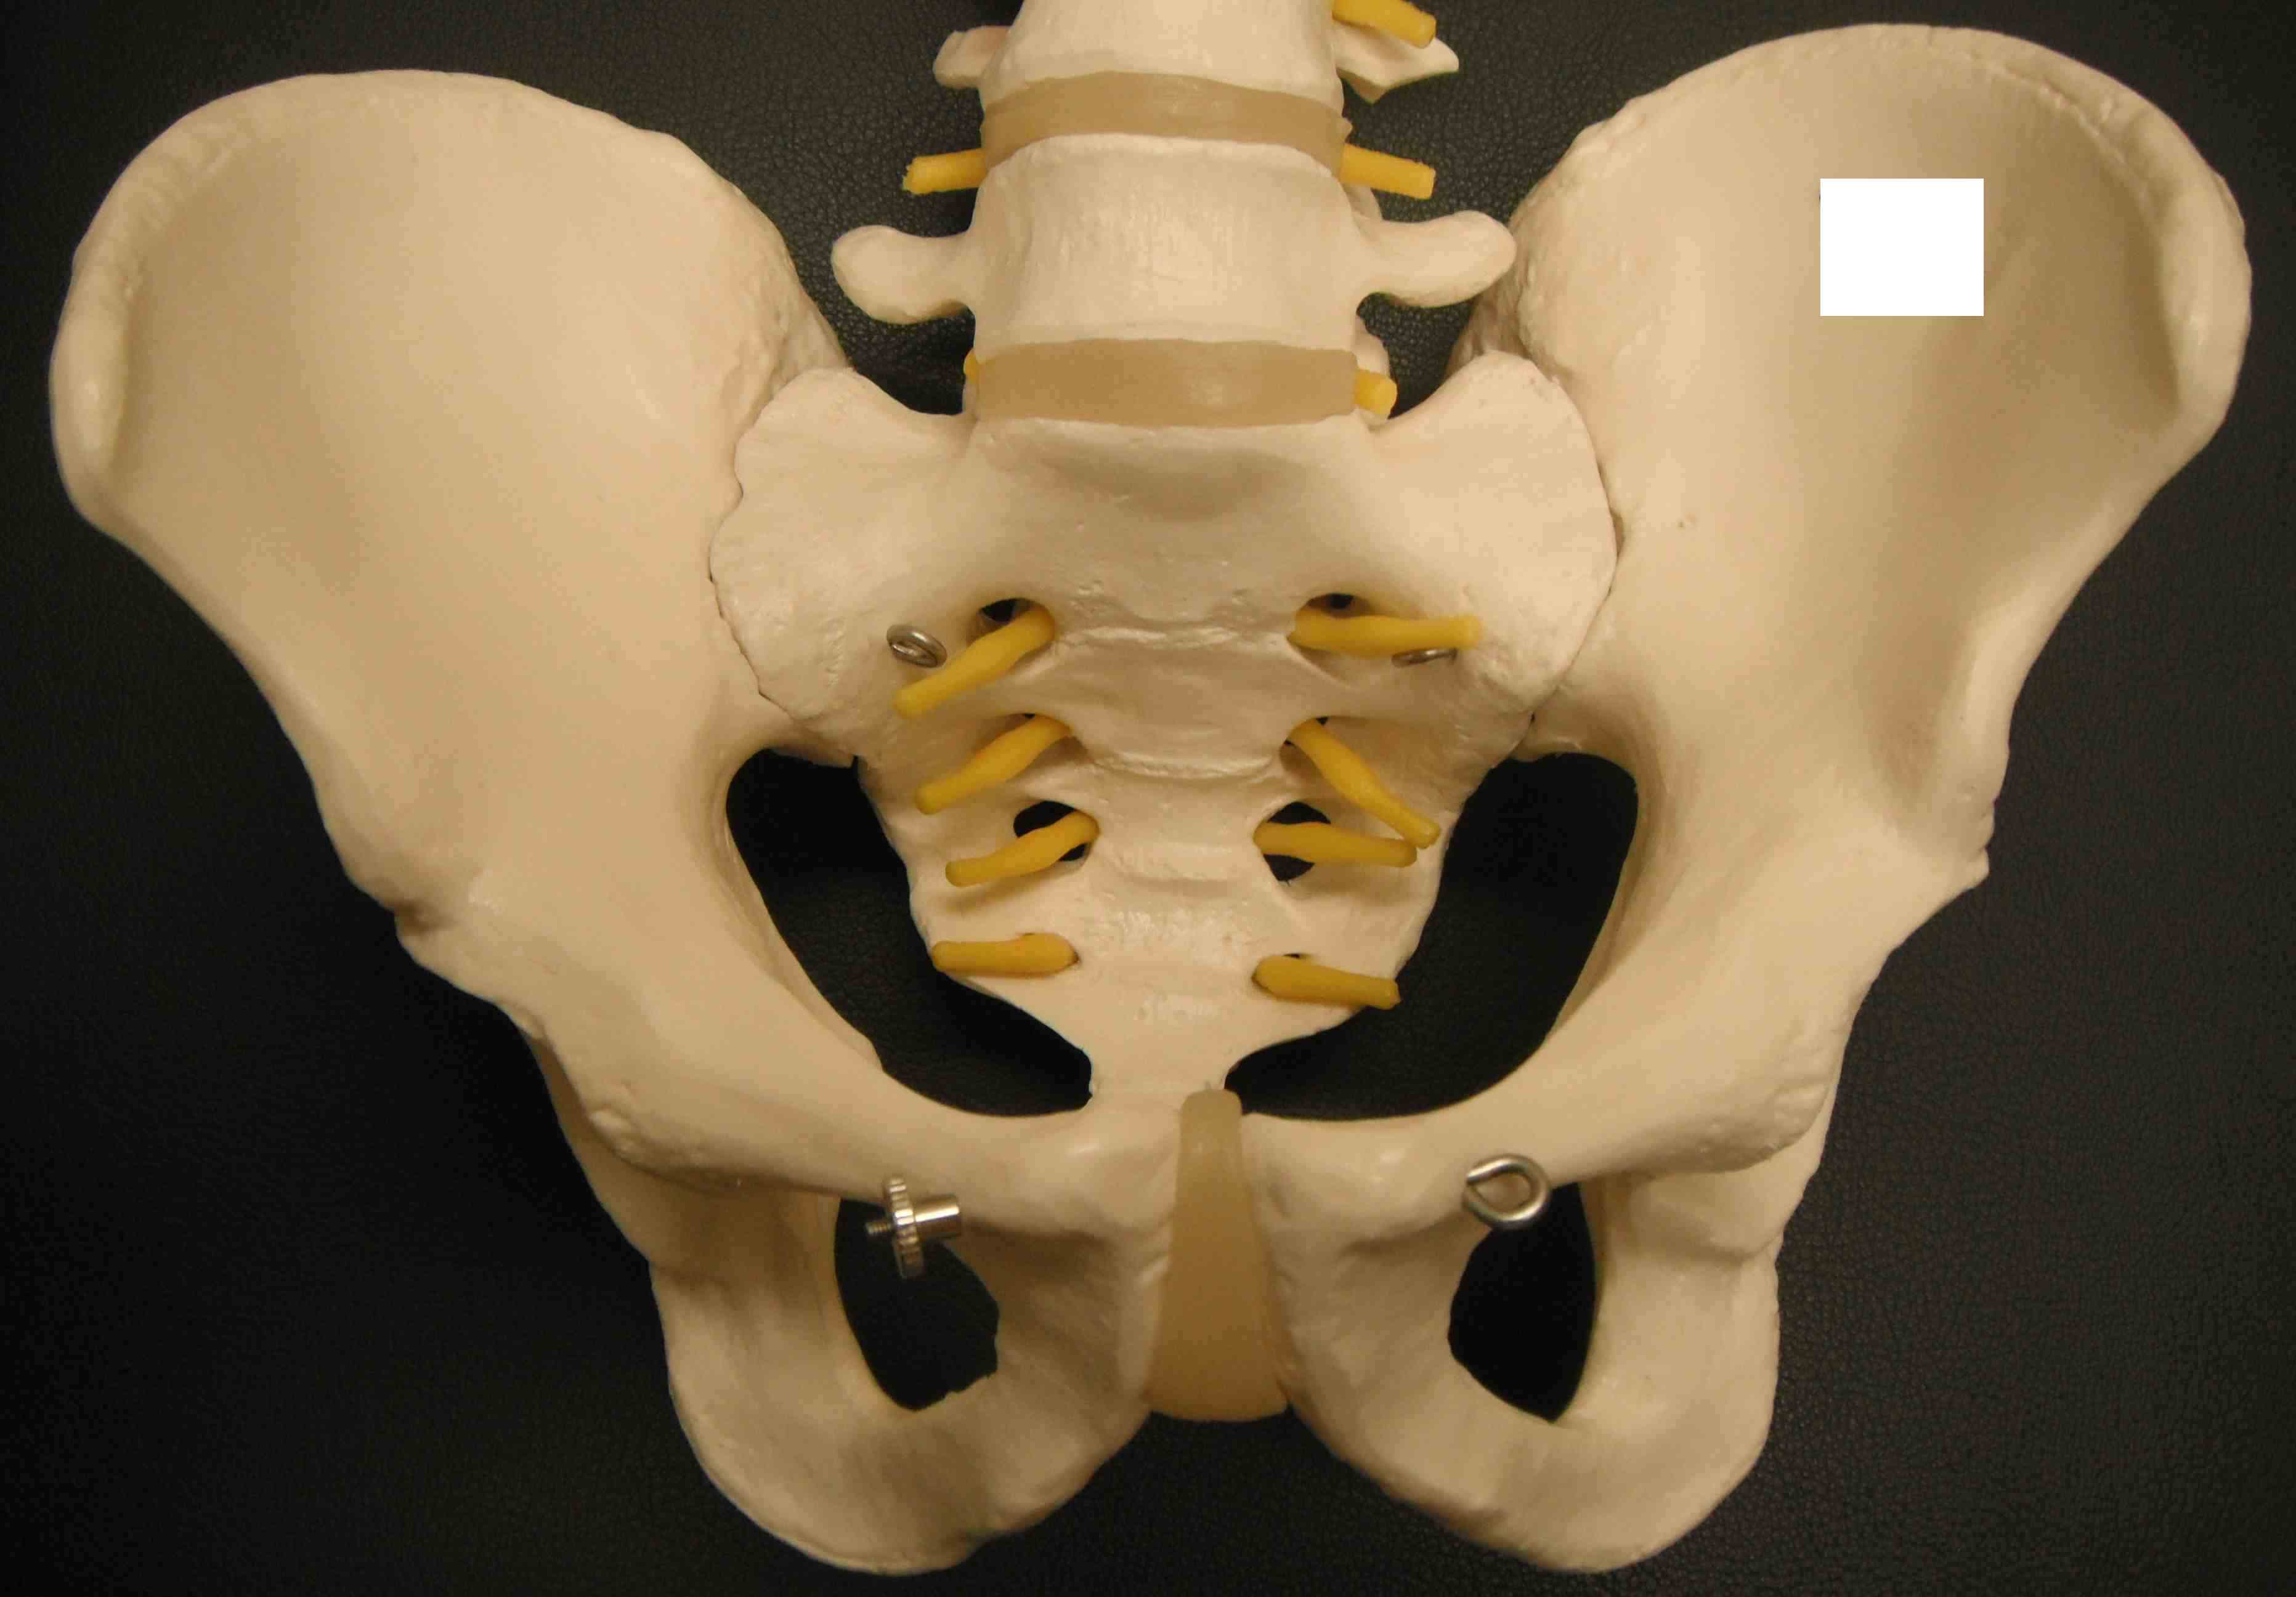

Background

Bony anatomy

Pelvic AnatomyPelvis Outlet

Soft tissue anatomy

Pelvis anatomy 1LIgaments pelvis posterior